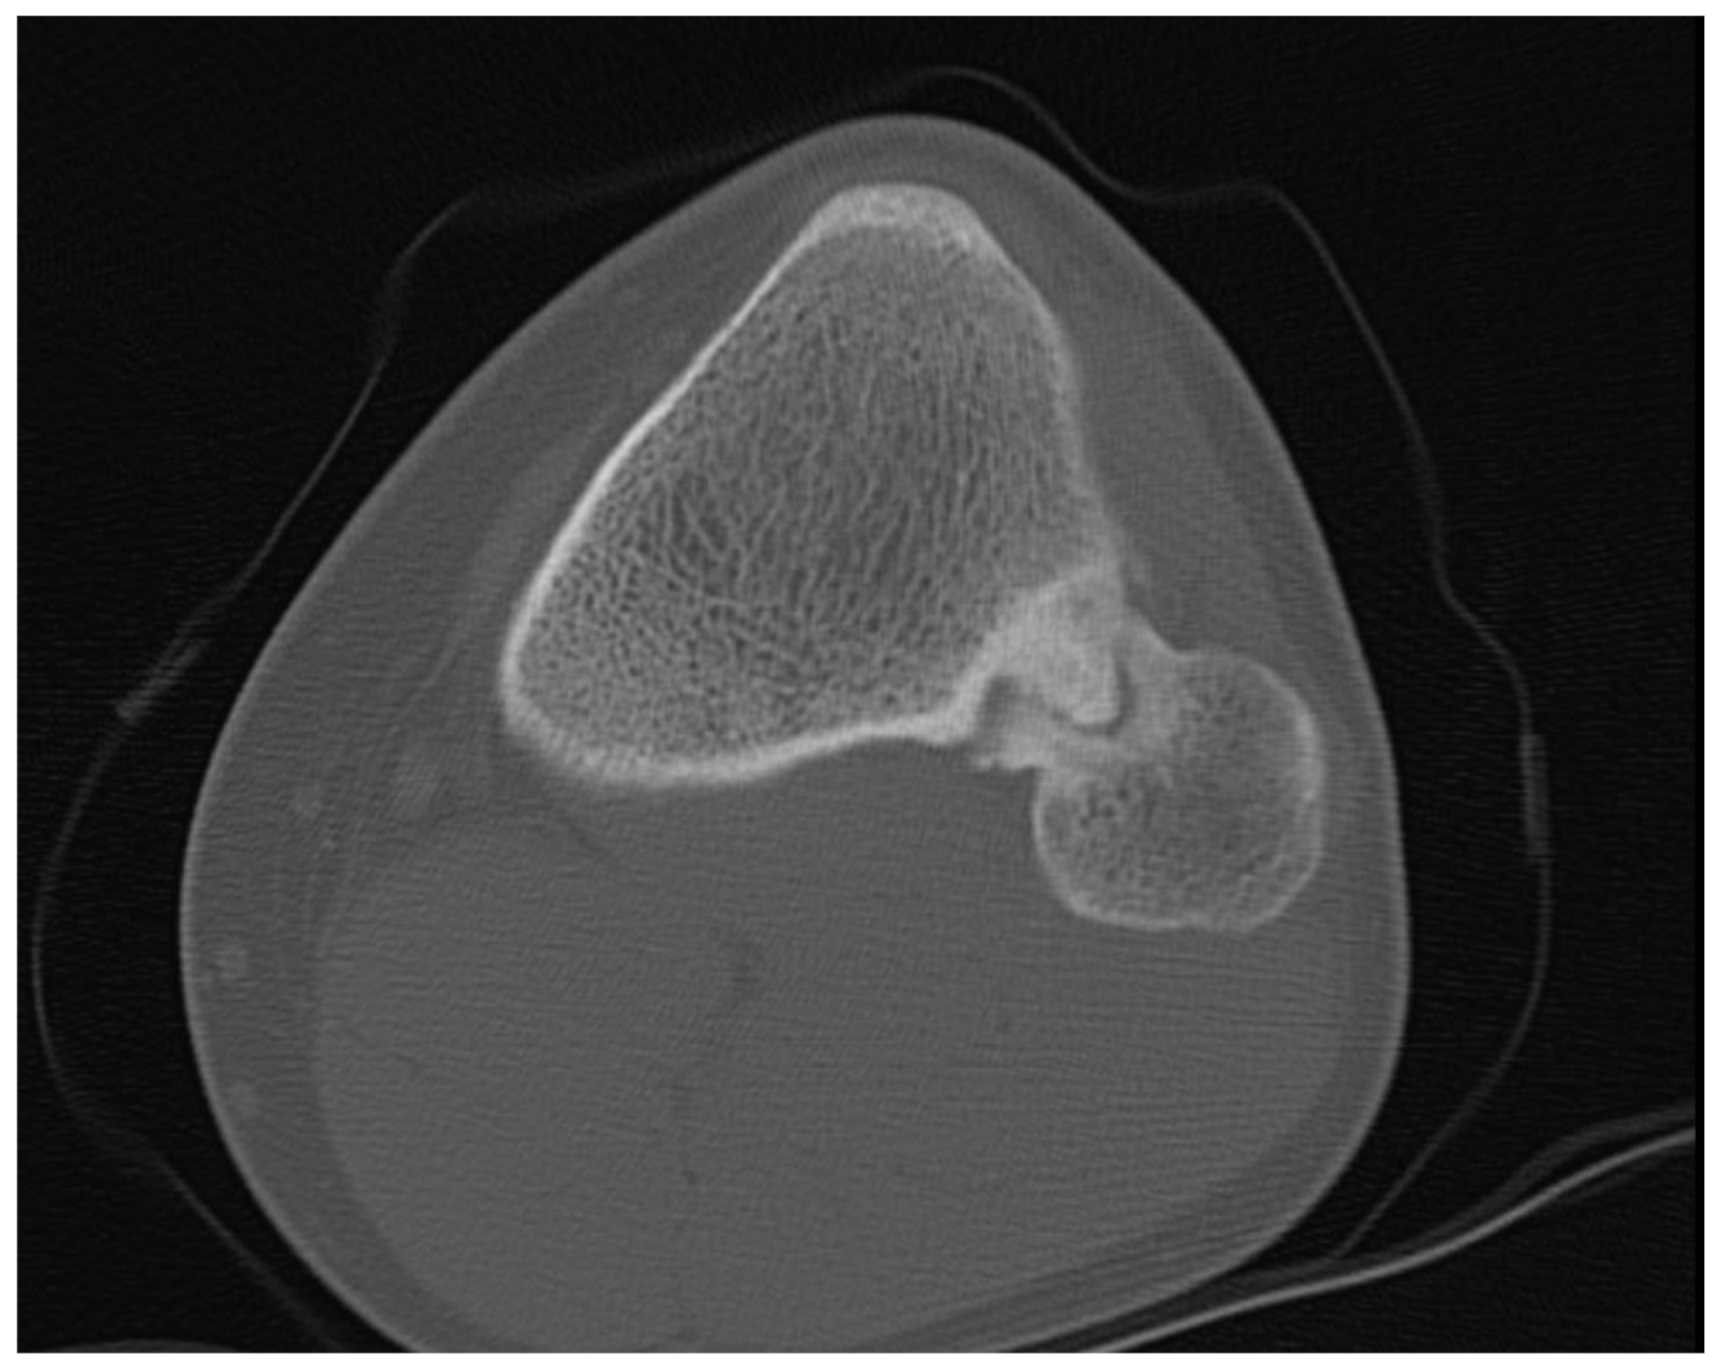

Plain radiographs, performed in anterior-posterior and lateral views of both knees showed a bony excrescence originating from the lateral tibial condyle as well as from the head of the fibula (Figure 1). The joint space was hardly visible. There were no signs of fracture or osteolysis.

Figure 1. Plain radiograph in a.-p. view showing the bilateral synostosis.